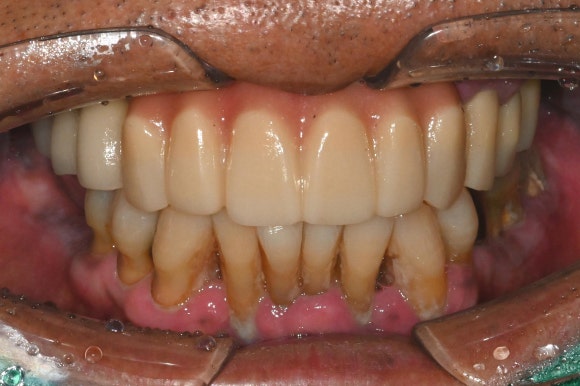

여기서 중요 포인트는,

잇몸을 누르지 않는 구조의

임시치아 라는 점입니다.

보통 치아를 바로 장착할 때는

시멘트를 사용하는 경우가 많은데,

이 시멘트가 잇몸 속에 남으면

염증을 유발할 수 있습니다.

그렇기에

시멘트 없는 구조로

장착하였습니다.

아직 실밥이

선명하게 보이는 시기지만

환자분은 바로

식사와 대화가 가능한 상태가 됩니다.

즉,

진짜 의미의 “원데이 보철” 이죠.

수술 전 후 사진을 비교해보면

더욱 명확히 들어납니다.